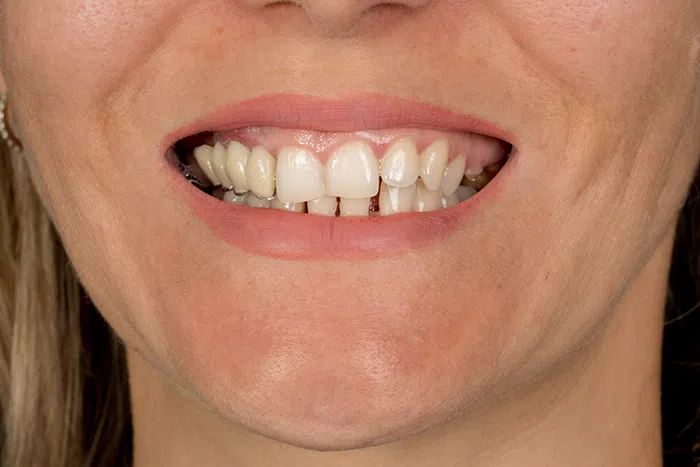

Înainte

Caz de estetică dentară – Fațete ceramică presată E-Max

Provocarea acestui caz a fost în prepararea minim invazivă a dinților centrali rotați și a obține o formă și o culoare cât mai naturală, pacienta dorind un caz de estetică dentară ce să nu fie observabil.

Pacienta a beneficiat de corecție gingivala cu laser pentru uniformizarea asimetriilor gingivale, tratamente endodontice de canal sub microscop, obturațiile vechi (plombe) schimbate cu materiale de compozit cu particule nanoceramice, și fațete dentare din ceramică presată E-Max.

Termen de finalizare 2 săptămâni de la amprentarea finală.